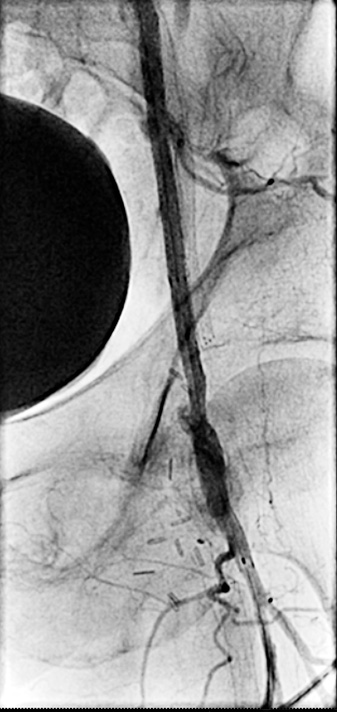

Figure 5. Baseline angiogram showing R CFA occluded stent jailing occluded profunda

Figure 6. Retrograde crossing from right profunda artery to the right external iliac artery

An angiogram showed patent abdominal aorta, bilateral common iliac arteries with existing stent, and occluded bilateral internal iliac arteries. The distal right external iliac artery had 60% stenosis. The left external iliac artery was patent. The right common femoral artery had an occluded stent jailing a known ostial CTO of the right profunda femoral artery, which filled poorly via collaterals. The right superficial artery was occluded.

We gained left femoral artery access with up-and-over technique sheath advance to the right external iliac artery. As expected, we failed to cross the right CFA occluded stent to the jailed right profunda. Ultrasound access was obtained in the right profunda femoral artery in a retrograde fashion. We probed the chronic total occlusion of the ostial segment of the right profunda and the CFA in retrograde fashion, but we could not get into the true lumen of the right external iliac. We then used the IVUS guided crossing device, “Pioneer,” and successfully crossed the occlusion of the right common femoral artery. The entire crossing passage was outside the existing occluded CFA stent and inside the wall of the CFA. The lesion was pre-dilated with a 5×20 mm PTA balloon and then a 6×40 mm PTA balloon. Despite the good release of the lesion at 10 atm, there was severe recoil post dilation of 80% residual stenosis. We inserted a 7×80 mm Zilver PTX DES stent into the right common femoral artery, followed by a balloon expandable short stent at the iliofemoral junction for persistent recoil.